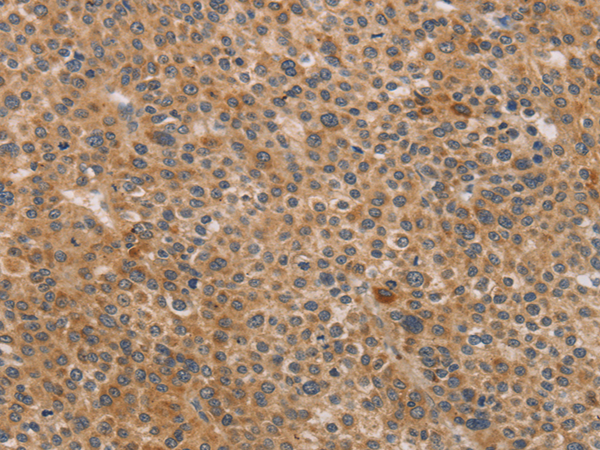

分类: 科研抗体货号: P04689别名: CLG4; MONA; CLG4A; MMP-2; TBE-1; MMP-II应用: WB,IHC反应种属: Human, Mouse, Rat